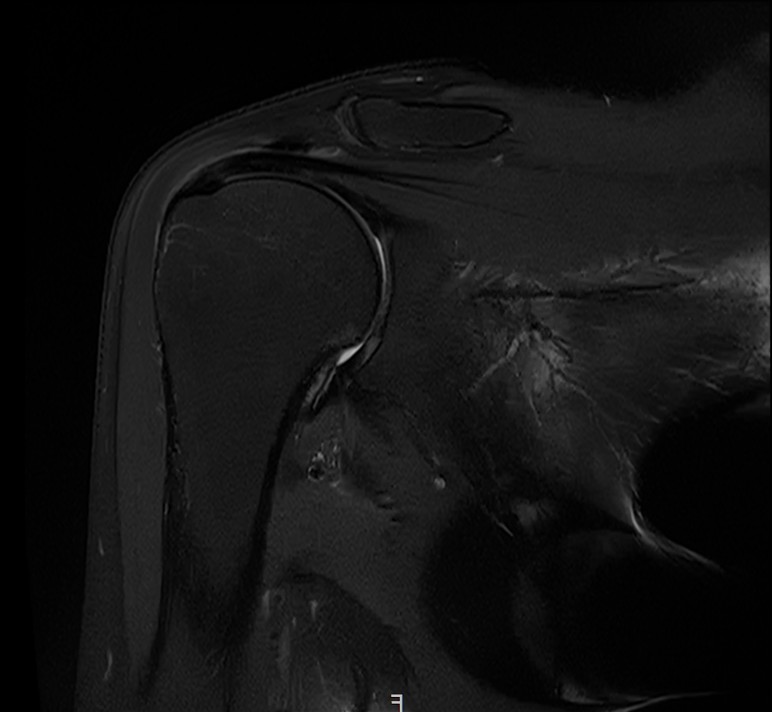

X-ray와 MRI, 초음파 검사를 시행했습니다.

진단 결과:

- ✓석회성건염: 극상건에 약 1.4cm 석회 (휴지기)

- ✓회전근개 관절면측 부분파열: 약 40%

두 가지 문제가 동시에 있었습니다.